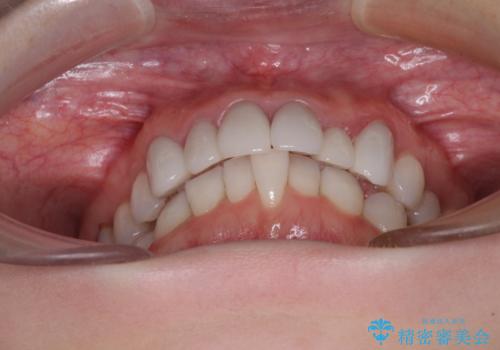

前歯のデコボコと奥歯の咬み合わせをインビザラインで改善

- 上下前歯のデコボコと奥歯の欠損を気にして来院された患者様です。

右下の欠損分は奥歯が倒れ込んでスペースがなくなっていたため、矯正治療により本来の位置に歯を移動させ、オールセラミックブリッジによる欠損補綴治療を行うこととしました。

全顎的にセラミッククラウンが多く装着されているため、インビザラインによる矯正治療を行うこととしました。

右下は移動量が多いため、十分な移動が達成されない場合はワイヤー装置を使用する予定としておりましたが、しっかりとマウスピースを装着してくださったため、前歯とともに十分に歯を動かすことができました。